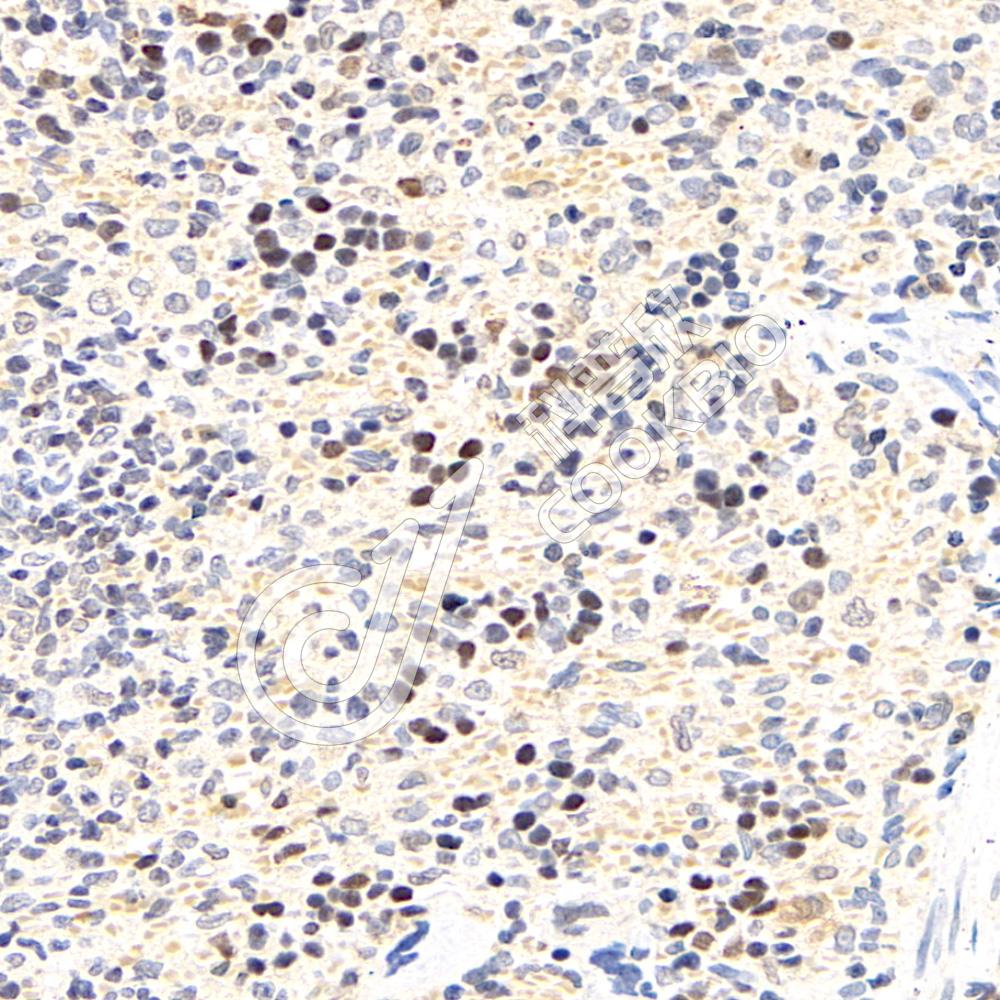

IHC检测CDK2蛋白(货号 K1336387).

样品: 人弥漫性大B细胞淋巴瘤, 4%多聚甲醛 (货号KSG1101) 固定12-24小时.

抗原修复: 柠檬酸抗原修复液(干粉, pH 6.0) (KSG1201), 98℃, 20分钟.

—抗: 1: 500稀释, 4℃ 孵育过夜.

二抗: S-vision免疫组化多聚二抗(山羊抗兔),即用型 (货号KB3906), 室温孵育20分钟.